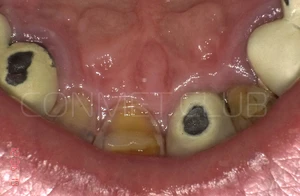

Через 3 месяца временная коронка удалена и начато изготовление стандартной металлокерамической коронки. Вид на имплантат КОНМЕТ сразу после удаления временной коронки.

Из-за глубокого резцового перекрытия пришлось сильно утачивать стандартный, прямой абатмент. Безусловно не самая простая ортопедическая ситуация с сложно прогнозируемым сроком службы.

Контрольное фото через 6 недель после окончательного протезирования. Почти идеальная сохранность межзубных сосочков.

По причине крайне малой высоты абатмента, палатинальную поверхность коронки оставили не покрытой керамикой. Толщина металлического колпачка в этом месте 0,3 мм.

Итоговое фото через 6 недель после окончания протезирования.